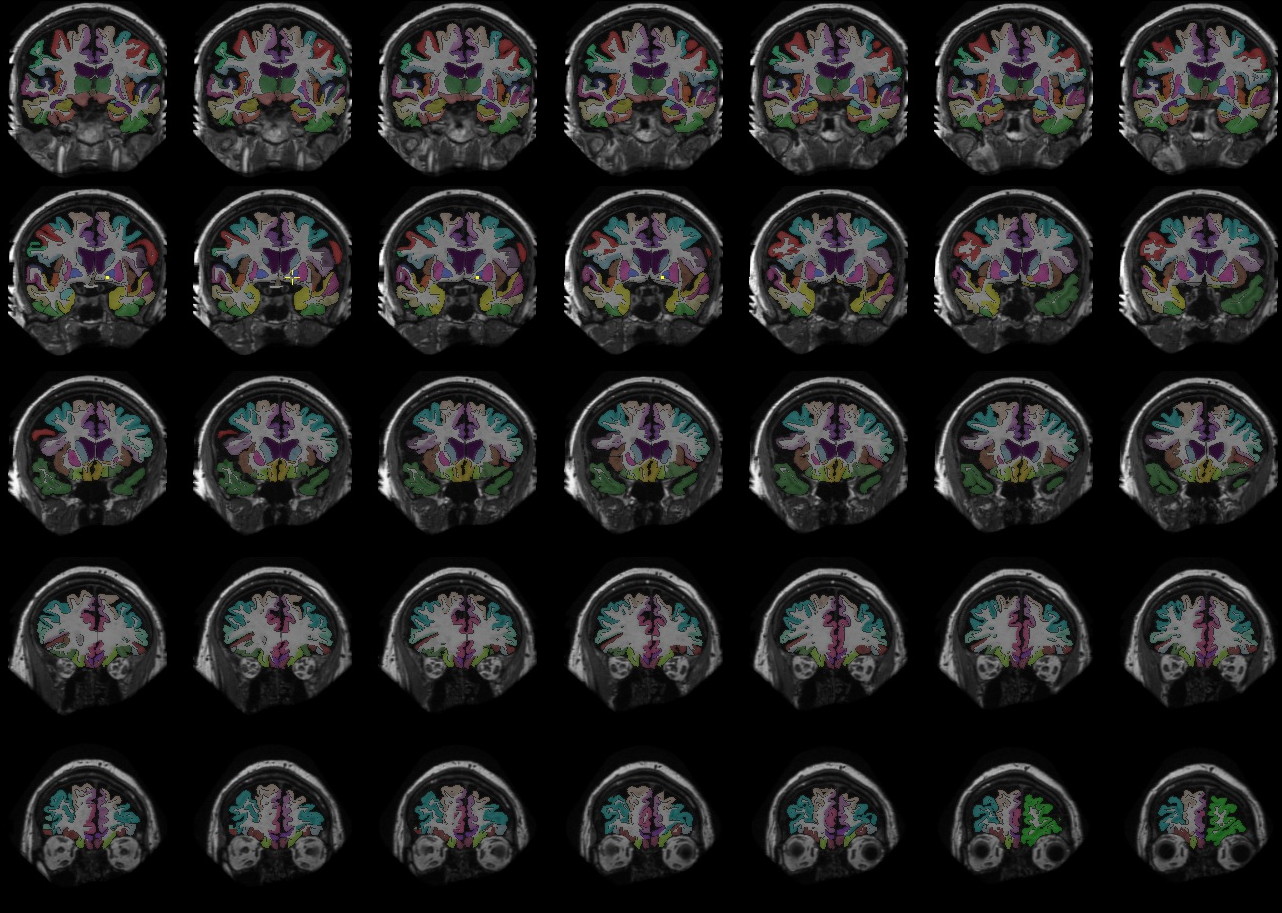

Manually Labeled MRI Brain Scan Database

Manually Labeled MRI Brain Scan Database Images

3 Images available.

Description:Older Subject

(click to enlarge)